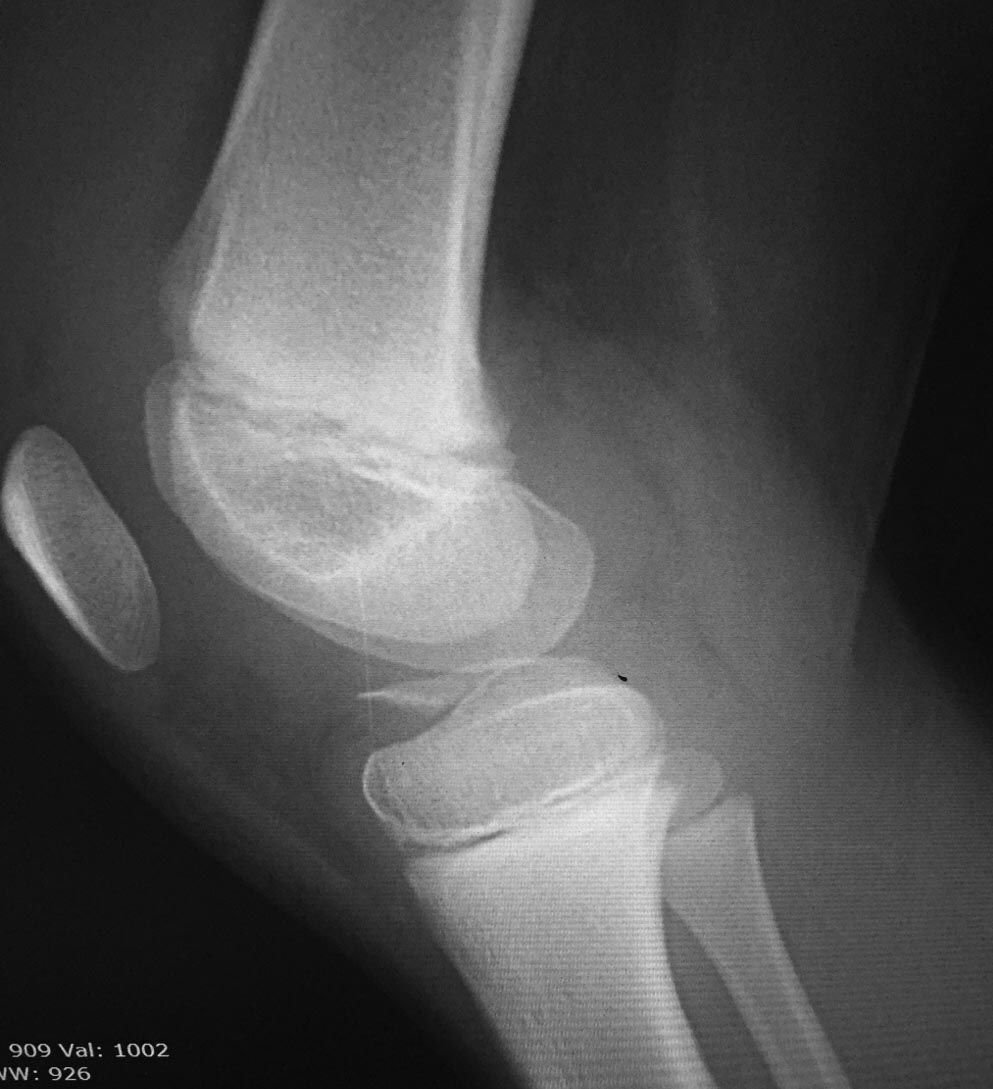

Пациент 8 лет, девочка. Перелом межмыщелкового возвышения по 2 типу.

Есть артроскоп, но все что мы можем сделать это диагностика, к

сожалению. Кто имеет опыт, подскажите, как лучше поступить. Заранее

благодарю.